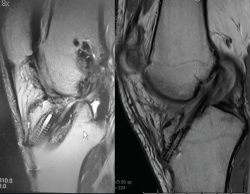

El estudio mediante TC, tanto en 2D como en las reconstrucciones actuales en 3D, va a ser de gran utilidad para poder identificar la posición de los túneles óseos tibial y femoral, la dirección de ambos y, finalmente, el grado de dilatación y la morfología de los mismos. Estos aspectos van a ser claves para poder planificar la cirugía de revisión en uno o dos tiempos (Figuras 3 y 4).

Figura 3. La tomografía computarizada en 2D mediante cortes axiales, coronales y sagitales permite conocer tanto la dirección como la morfología de los túneles previos, así como medir el grado de dilatación de los mismos para planificar la cirugía de revisión.

La RM será útil para conocer la situación de las partes blandas intraarticulares: restos de la plastia del LCA previa, valoración de posibles lesiones asociadas, defectos meniscales previos, lesiones condrales, etc. (Figura 5).

Figura 4. Actualmente, la reconstrucción en 3D de la tomografía computarizada permite comprender mejor la localización tridimensional de los túneles óseos.

Figura 5. El estudio mediante resonancia magnética permite evaluar la situación de la plastia del ligamento cruzado anterior, así como del resto de las estructuras intraarticulares.